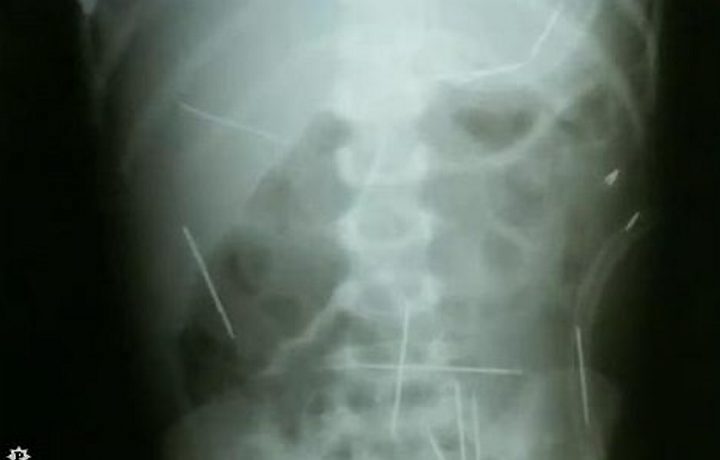

Se não obtiver sucesso com a tese da inimputabilidade ou da semi-imputabilidade, a defesa de R.C.M. pode tentar desclassificar o crime de tentativa de homicídio qualificado para o delito de lesão corporal grave(art.129, §1º, inciso II, CP), cuja pena é de 1 a 5 anos de reclusão. A lesão pode ser classificada como grave porque a criança, de 2 anos, foi submetida a três cirurgias no Hospital Ana Néri, em Salvador para a retirada de agulhas espetadas em órgãos vitais, o que ocasionou evidente risco para a sua vida. Esta sanção pode ser aumentada de um terço – crime contra menor de 14 anos (art. 129, §7º, CP) – e de mais um terço – crime cometido no contexto de violência doméstica (art. 129, §§9º e 10, do CP).